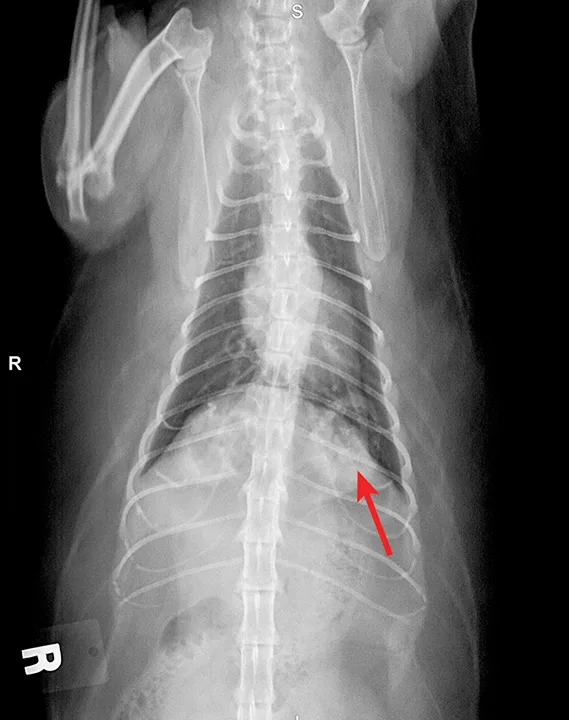

Radiographic evaluation is variable. Classic cranioventral distribution is less common in cats (Figure 3). A bronchial pattern is most common; however, bronchointerstitial, alveolar, and more structured pseudonodular patterns can occur.6,8 Occasionally, pulmonary abscesses may be appreciated and resemble pulmonary neoplasia (Figure 4).

FIGURE 3

Radiograph of bronchopneumonia with more classic cranioventral distribution (arrows). Other diseases, including CHF, have a similar distribution. Lack of this pattern does not rule out infection.